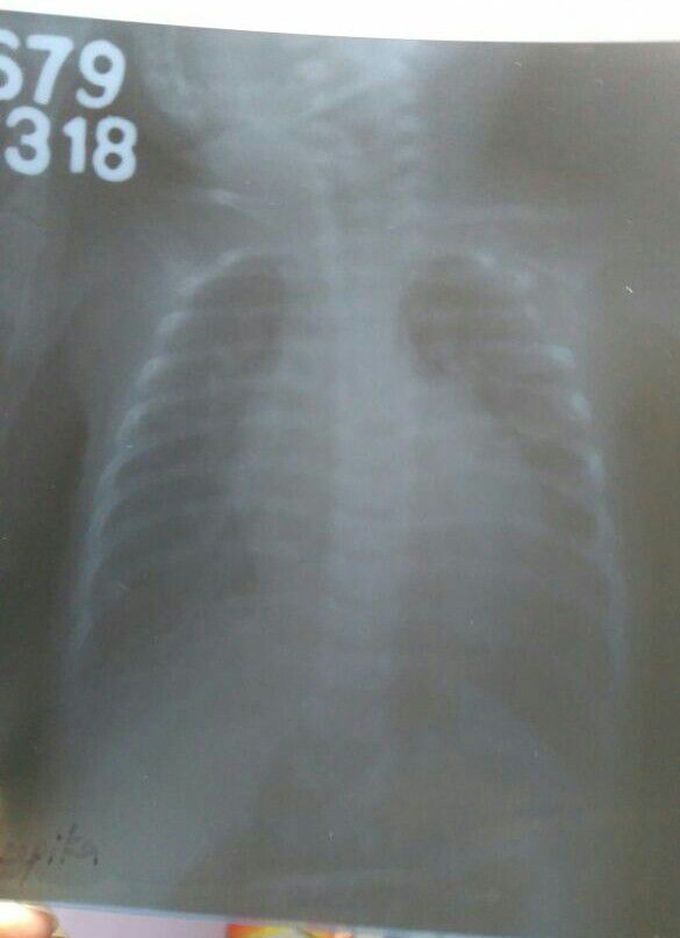

Cardiomegaly

Cardiomegaly in 5 months old baby.